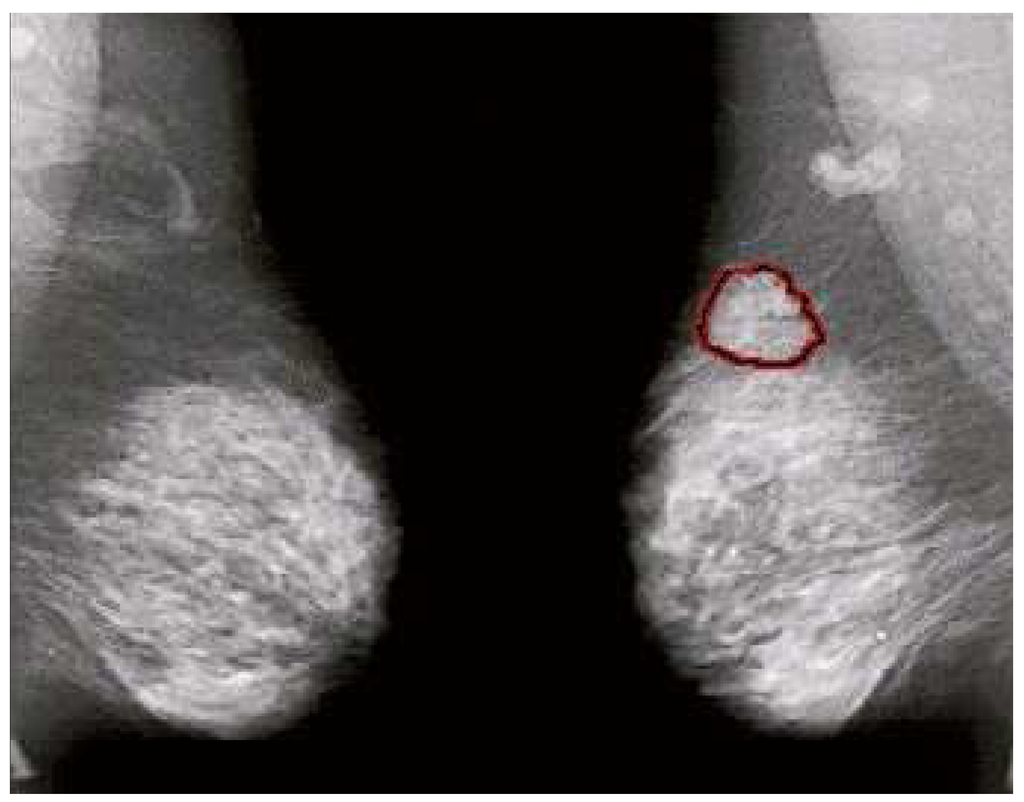

Figure 5. Mammograms of left and right breasts with cancerous area outlined. The similarity of texture between cancerous and normal tissue makes asymmetry an important tool in cancer detection.

An effort was made to provide image classifications and to develop a distance function for CAD of medical images as well as to explore the properties of the dataset. This initial approach utilizes filtering followed by spatial symmetry analysis using a variant of supervised clustering to determine an overall measure of similarity by combining the contextual similarity of the filtering with the spatial similarity of the analysis. This can be a useful measure for diagnosing mammograms (or for pre-screening) since only an overall determination of cancer or no cancer is required. A secondary goal of our work is to determine the importance of similarity or asymmetry in the computer analysis of mammograms. Figure 5 shows why spatial asymmetry is important in finding cancers in mammograms since we see that the texture and appearance of cancer are both very similar to the texture and appearance of normal tissue in the breast. Our analysis starts with filtering to find the contextually similar suspicious points that could be cancers in the mammograms. The AFUM filter was used, which highlights the areas of the image that have bright cores, a characteristic of spiculated lesions, and is shown in Figure 3b. The filter results are used to rank the output and only the top thirty-two are kept. Although it may not be the optimal choice of filtering, the spatial analysis can be applied to any technique that can rank the suspiciousness of areas. The number of points returned by the filtering step is one of the variables that were learned in optimizing the analysis. Alternatively, a threshold on the suspiciousness value could have been used instead of taking the top few. However, the top few were chosen in order to try to be insensitive to image processing choices. The filter results varied significantly from image to image, which might have biased the analysis if thresholds were used.